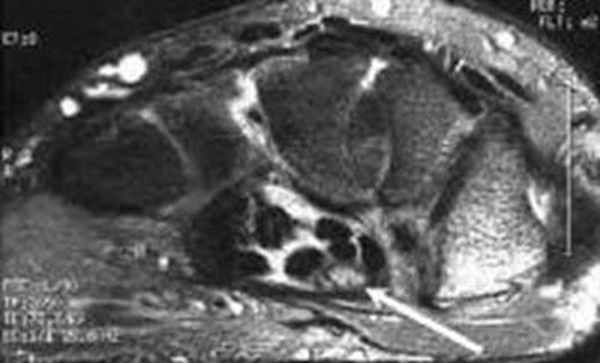

Результат МРТ правого лучезапястного сустава (рис. 2), подтвердил клиническое предположение о повреждении ладьевидно-полулунной связки, который заключался в нарушении целостности структуры связки. Также были выявлены признаки асептического некроза ладьевидной кости в стадии отека костной ткани.

Рис. 2. МРТ-исследование правого лучезапястного сустава. Получены протон взвешенные изображения с подавлением сигнала от жировой ткани (PD FAT SAT) в аксиальной, сагиттальной и фронтальной плоскостях, Т1 взвешенные изображения во фронтальной плоскости. На полученных сканах определяется: 1 – увеличение ладьевидно-полулунного сустава вдвое по сравнению с соседними; 2 – вдоль оси ладьевидной кости отмечается скопление жидкости, что можно расценить, как продольный перелом ладьевидной кости, либо отек костной ткани

После операции лучезапястный сустав фиксировался иммобилизационной повязкой сроком на 4 недели. По окончанию срока иммобилизации пациентке была рекомендована постепенная разработка лучезапястного сустава, исключающая осевые нагрузки. Через 6 недель с момента операции пациентке было выполнено МРТ исследование для осуществления контроля положения восстановленной связки (рис. 5).

Рис. 5. МРТ исследование правого лучезапястного сустава. На МРТ сканах во фронтальной плоскости: 1) отмечается восстановление пространства между ладьевидной и полулунной костями, отчетливо видна связка; верифицируется биодеградируемый пин и якорный фиксатор в ладьевидной кости; 2) отмечается синовит лучезапястного сустава и отсутствие отека костной ткани ладьевидной кости